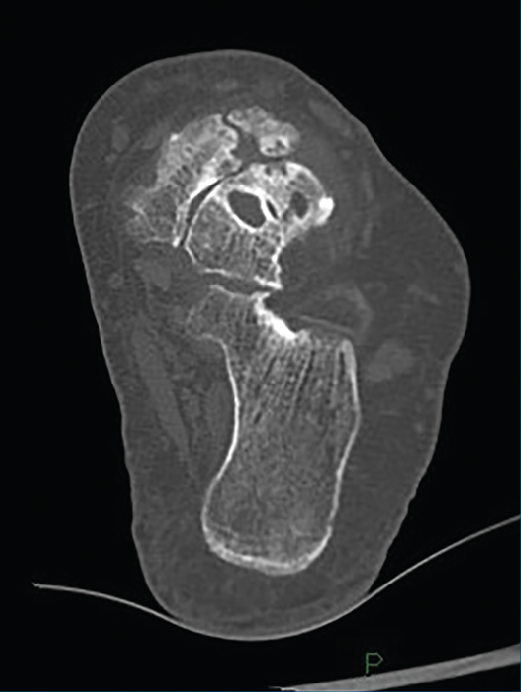

Introducción y objetivos: la enfermedad de Müller-Weiss (EMW) es una patología causada por la displasia del navicular que, en muchos casos, está mal o infradiagnosticada. Se presenta como un “pie plano-varo paradójico” y una artropatía talonavicular. En este trabajo pretendemos explicar nuestra experiencia con una cirugía de preservación articular –osteotomía “supervalguizante” de calcáneo aislada (de tipo Dwyer con desplazamiento lateral)– en nuestra primera serie de pacientes a los que no se realizó una artrodesis.

Material y métodos: estudio descriptivo retrospectivo de una serie de 17 casos de EMW en 15 pacientes operados en nuestra Unidad de Pie y Tobillo (2007-2015). Analizamos diferentes parámetros a través de la historia clínica, la exploración física, el estudio radiológico y escalas de valoración estandarizadas (escala visual analógica –EVA–, American Orthopaedic Foot and Ankle Society –AOFAS– y Likert).

Introduction and objectives: Müller-Weiss disease (MWD), a tarsal navicular dysplasia, is often misdiagnosed or underdiagnosed. Clinical presentation as a paradoxical “flatfoot varus” combines with arthritic talonavicular changes. In the present study we show our experience with a joint-preserving surgical treatment –isolated “super-lateral-slide osteotomy”– in the first series of patients in which a tarsal arthrodesis was not performed.

Material and methods: we present a descriptive, retrospective study of a series of 17 MWD cases in 15 patients that underwent surgery in our Orthopaedic Foot and Ankle Unit (2007-2015). We analyze different parameters through the clinical history, physical examination, complementary tests and standardized evaluation scales (visual analogue scale –VAS–, American Orthopaedic Foot and Ankle Society –AOFAS–, and Likert).